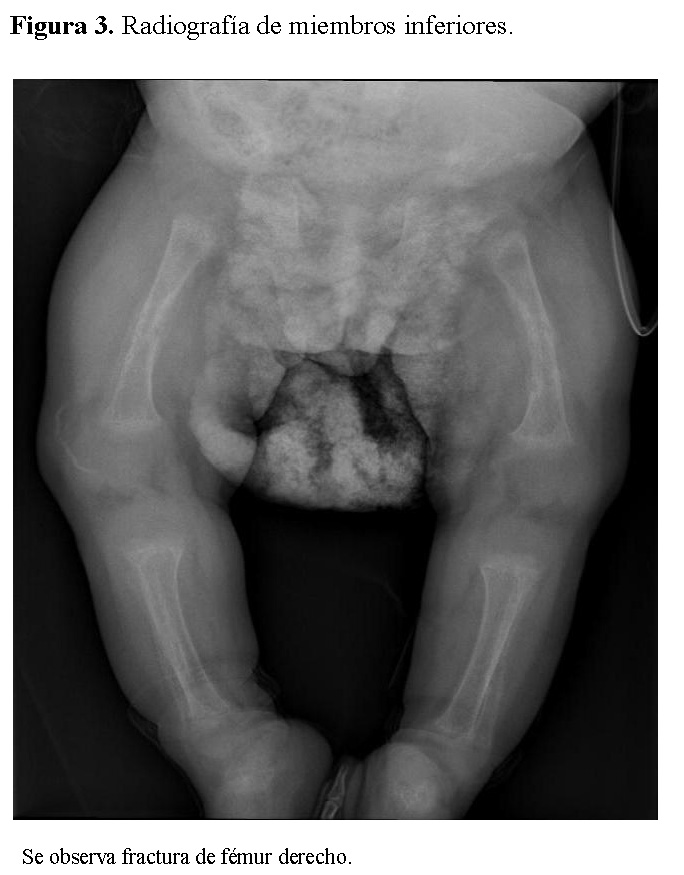

Chest radiography showed bilateral heterogeneous parenchymal infiltrates, pleural thickening, and right-sided rib fractures in the consolidation phase (Figure 1). Radiographs of long bones revealed severe osteopenia, periosteal reaction, and multiple pathological fractures, including the right and left humerus, right ulna, and right femur (Figures 2 and 3).